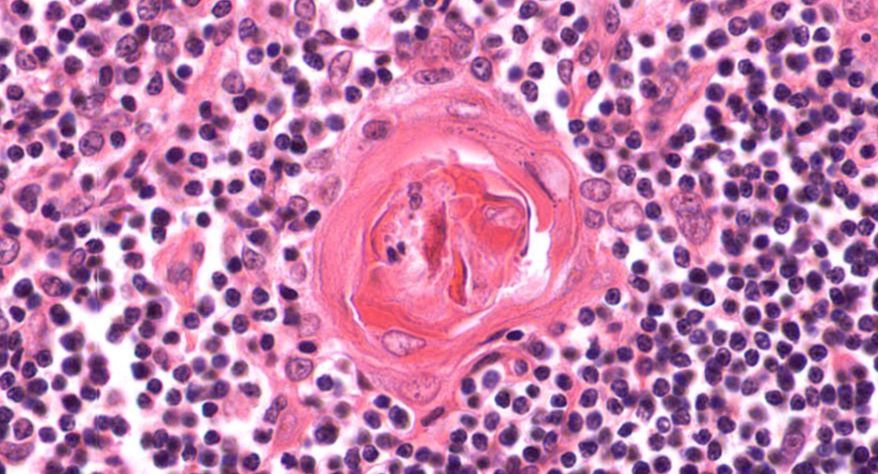

低倍镜:胸腺表面包有薄层结缔组织构成的被膜,结缔组织深入实质,将胸腺分成许多不完整的小叶。每个小叶分为周围的皮质和中央的髓质两部分。皮质中胸腺细胞排列密集,故染色深;髓质中胸腺细胞较少,胸腺上皮细胞多,故染色浅,其中可见染成红色的圆形小体-胸腺小体。高倍镜:胸腺小体大小不等,由几层至十几层扁平的胸腺上皮细胞呈同心圆状排列而成,其外周的细胞较幼稚,细胞核明显;小体中央部分的上皮细胞已退化,细胞核消失,胞质呈均质状,染成红色。

7.胸腺小体1

8.胸腺小体2